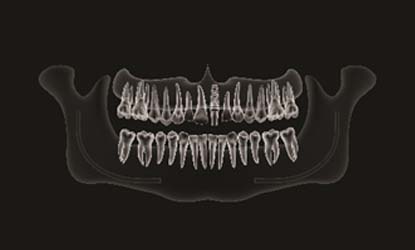

Problema: Trūksta priekinio danties

Tikslas:

Pakeisti trūkstamą dantį dantų implantu

Rezultatas:

Atkartota natūrali estetika